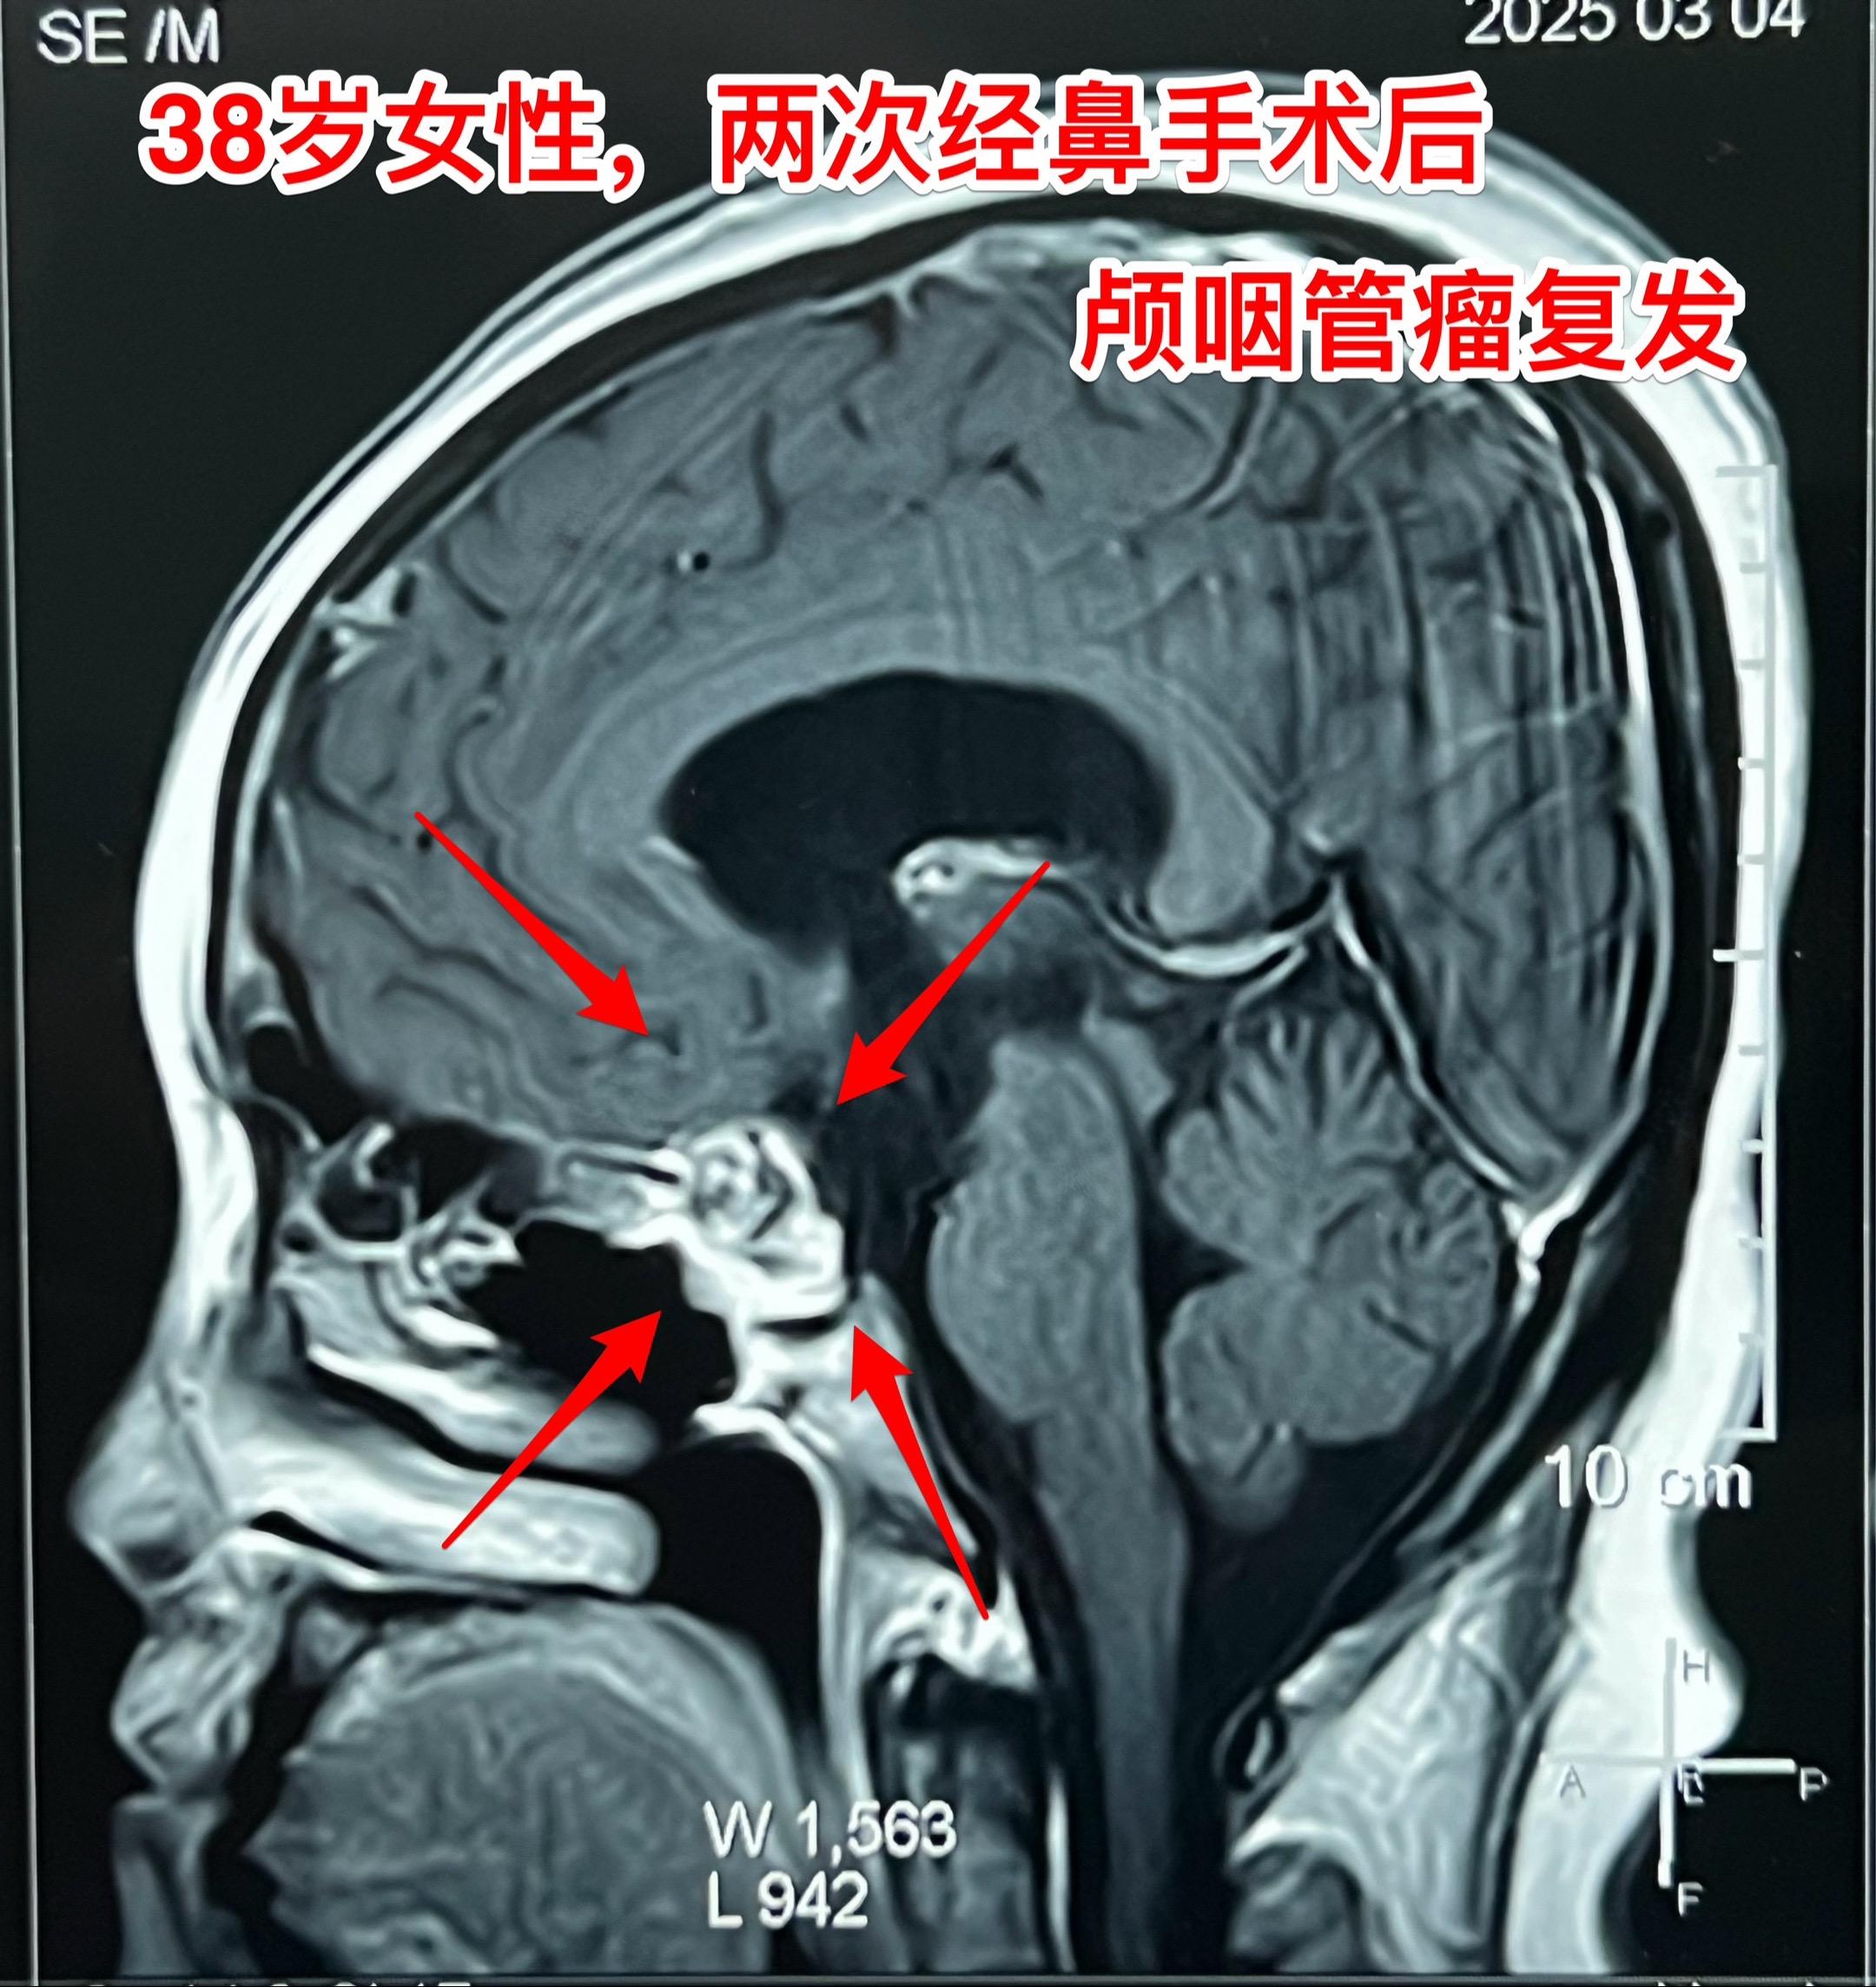

昨天的第四个手术(经鼻复发颅咽管瘤)昨日第四个完成的手术,是38岁女性,因为颅咽管瘤在北京某军医院先后作了两次经鼻内镜手术切除肿瘤。过年后发现肿瘤又复发了,见图。病人的左眼视力很差,属于无效视力。 手术结束时已是今日凌晨了!肿瘤从垂体窝向左侧生长,得到完全切除! 今日头部CT结果是满意的,病人从ICU转回了普通病房。希望肿瘤不再复发。